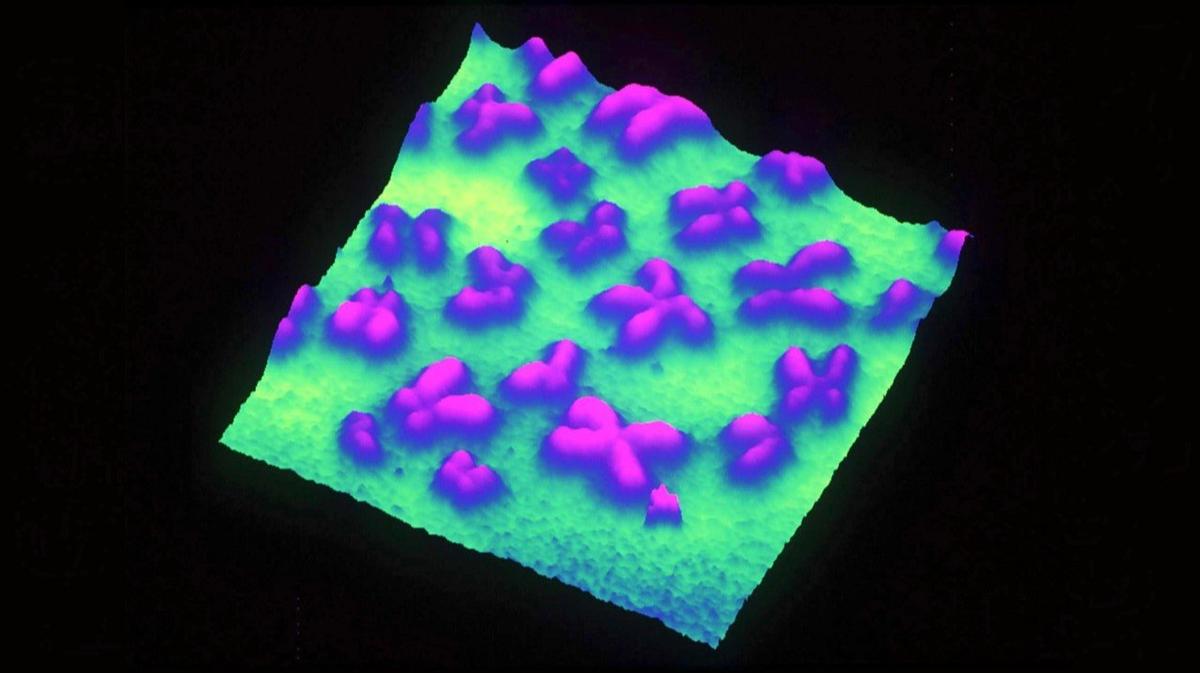

Nature: лекарство «Молнупиравир» от COVID-19 может приводить к опасным мутациям вируса